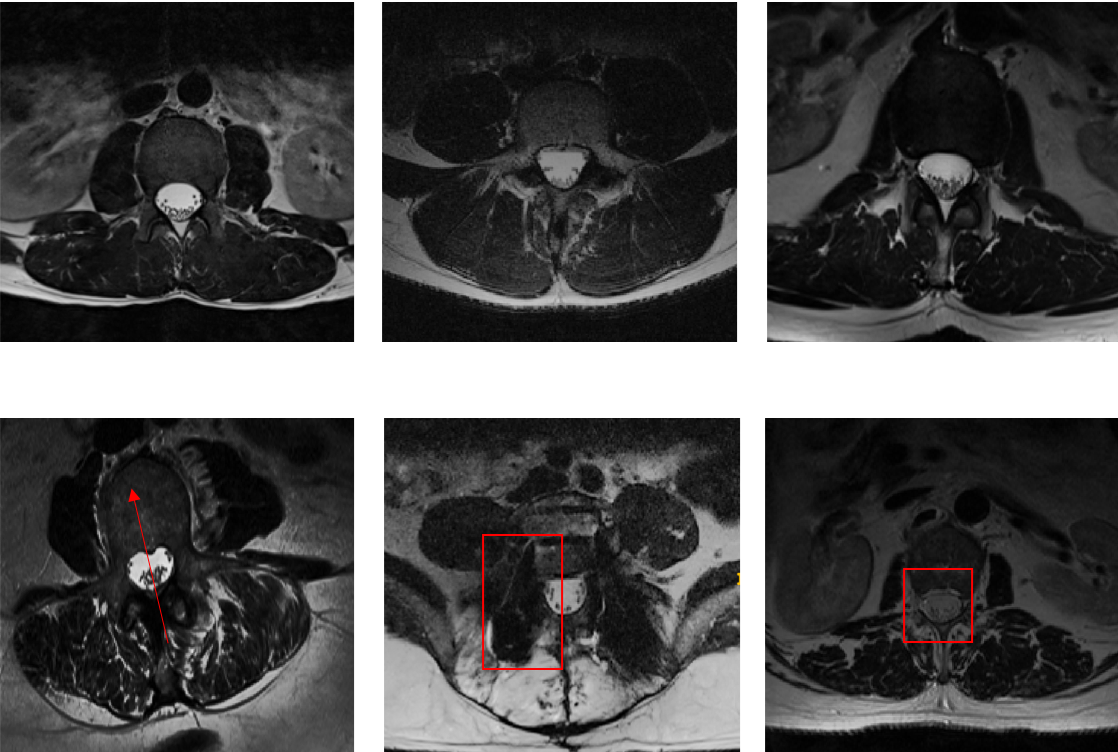

Manual segmentation of spinal canals was performed by two medical students using ITK-SNAP [32] and validated by a attending physician. The manual segmentation data were used as ground truth for all experiments presented here. The tasks we focus on consists of image segmentation of spinal canals and inter-vertebral disks on MRI data. We have previously published on this task, and enumerated challenges involved in the process. Examples of intervertebral disk segmentations and spinal canal segmentations are shown in figure2.

Refer to caption

Figure 2: Illustration of intervertebral disk and spinal canal segmentation